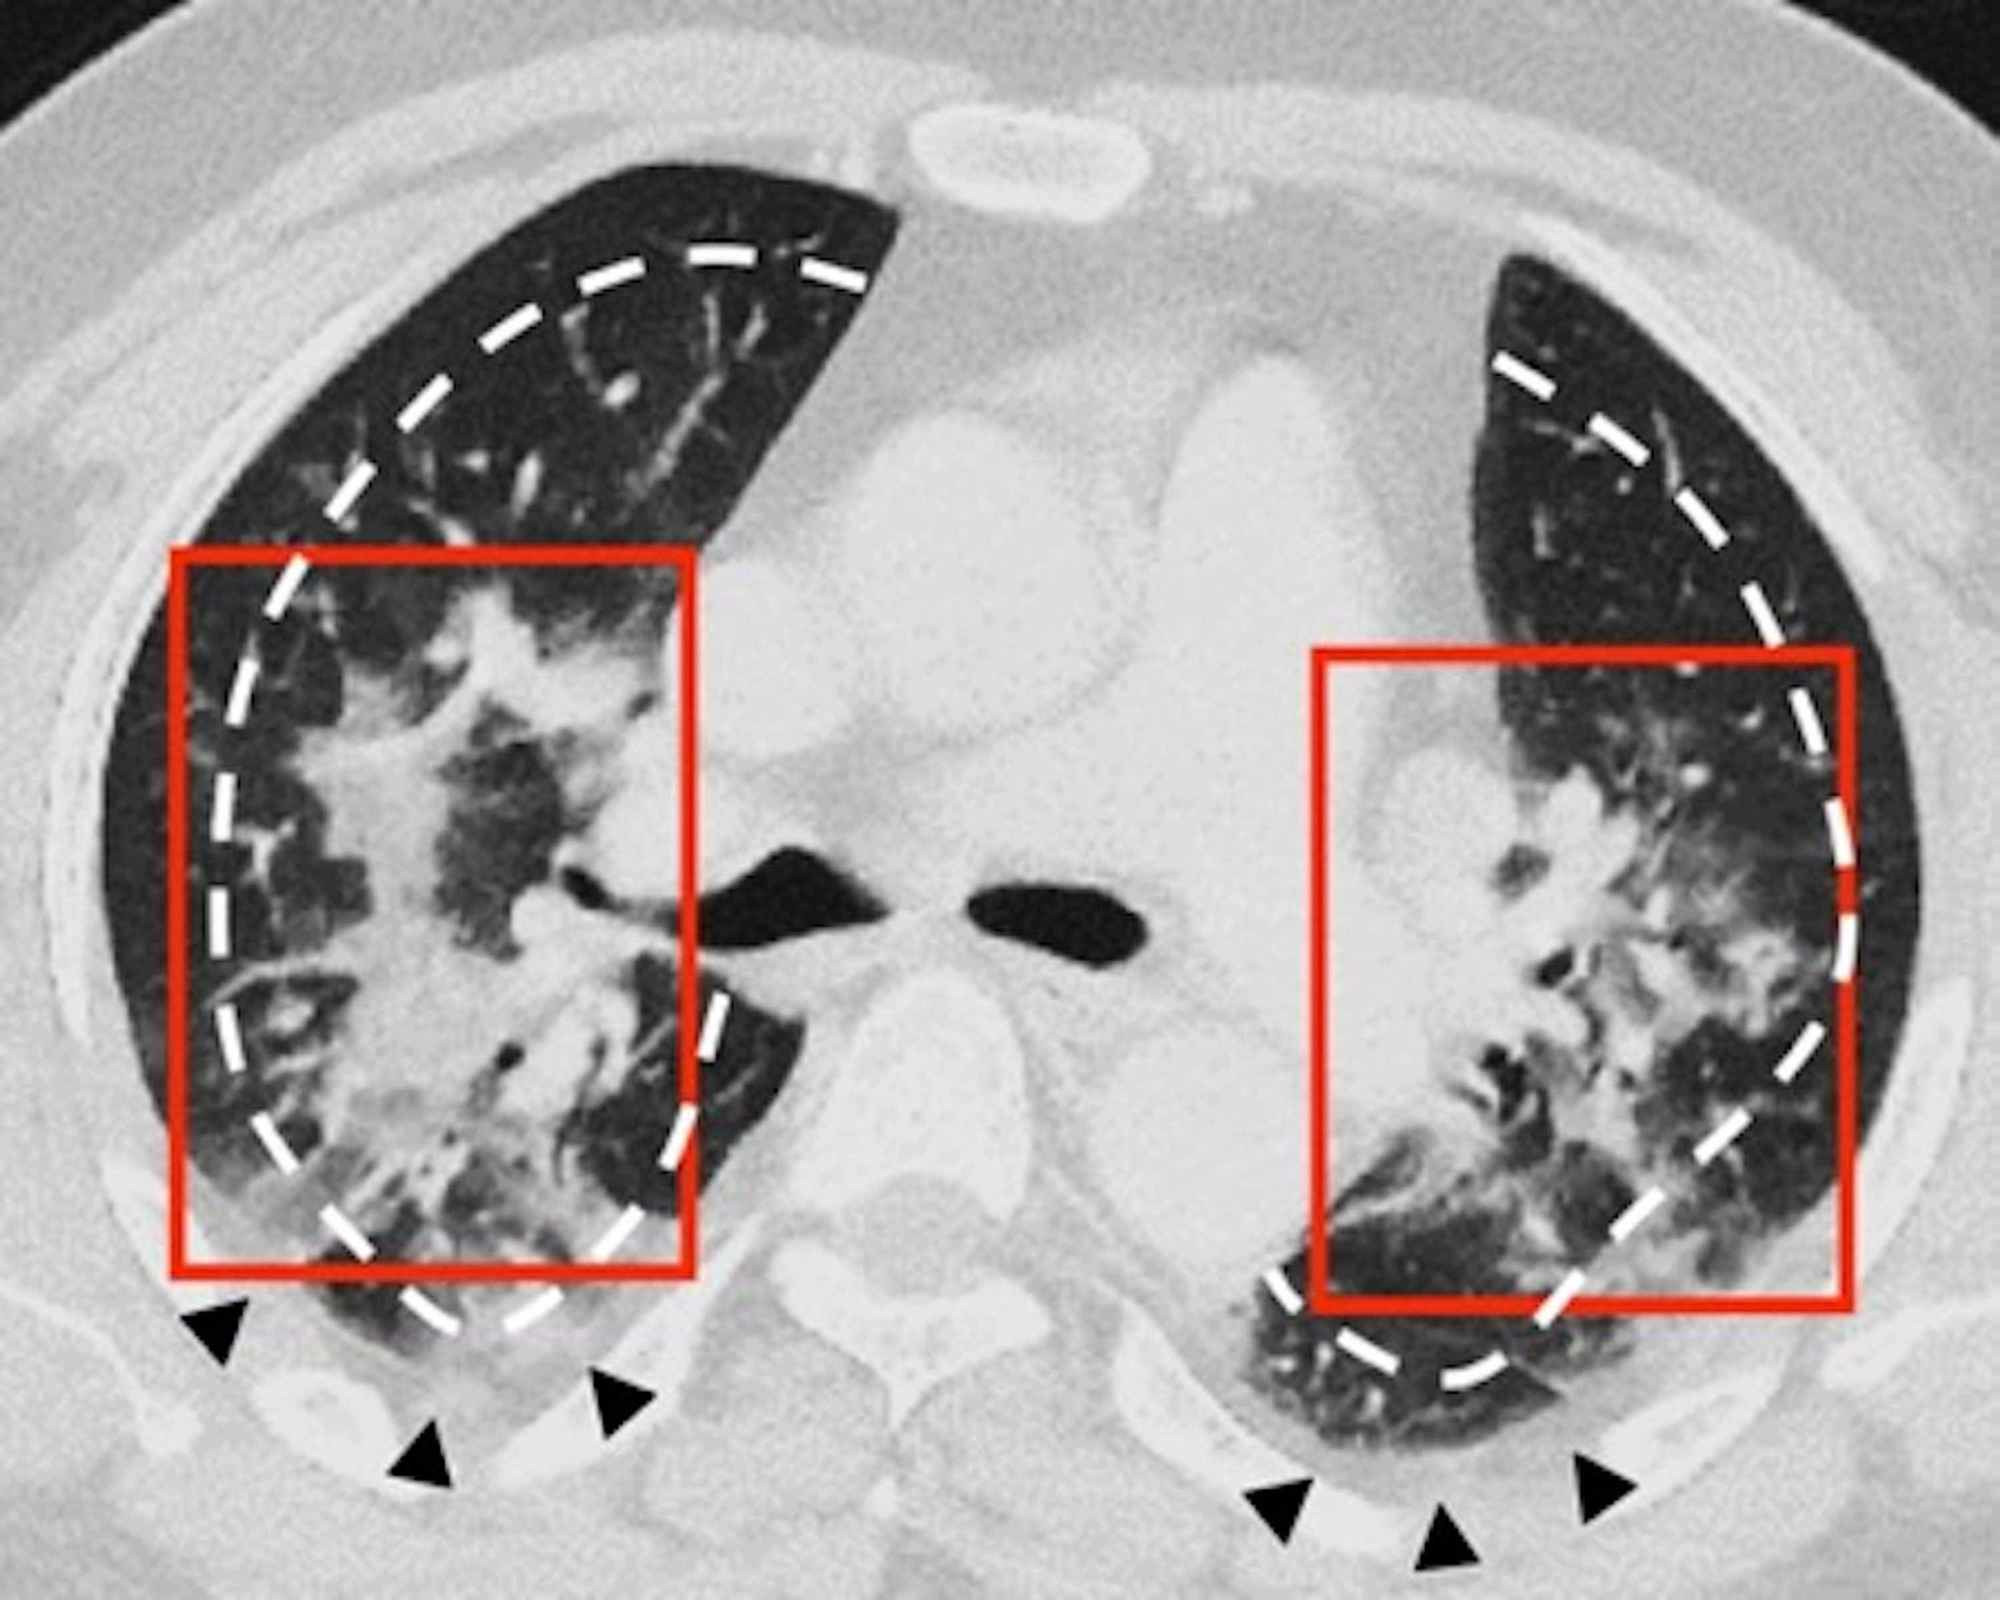

In the CT images, GGO plus consolidation was observed bilaterally in all 18 (100%) patients. No pure GGO or pure consolidation was encountered in our cohort. The predominant shape was amorphous (72%). Lesions showed no specific lobar predilection, but most lesions were localized posteriorly and peripherally.

The distinctive CT features in our cohort are summarized in Table 3, including GGO and consolidative patchy mostly amorphous (72%) lesions, bilateral posterior and peripheral multi-lobar lung involvement, pleural effusions, subpleural fibrotic lines, subpleural sparing, vascular engorgement, occasional crazy paving, occasional mediastinal lymphadenopathy, pleural thickening, lack of cavitation, and absence of reverse halo (atoll) signs.

Subpleural sparing, which was observed in this patient cohort, has never been reported before, whereas mediastinal lymphadenopathy has been reported occasionally in the literature in English [11]. Focal vascular engorgement, septal thickening, and a subpleural fibrotic line were seen frequently in our cohort, with frequencies of 83%, 72%, and 61%, respectively.

Patients’ CT features are presented in detail in Figures 3, 4, 5, 6, 7, 8. A majority of cases (56%) had moderate severity scores. There was no correlation between the severity score and mortality, p=0.790 (Table 4).